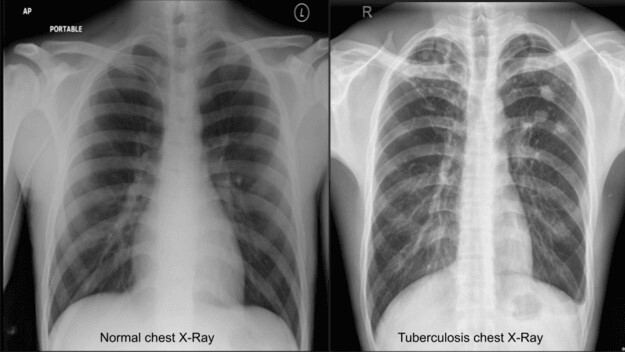

In this study, we used CXR images to detect TB. In Figure 3, CXRs of a healthy (healthy control case) person and a TB patient are depicted for visualization and comparison.